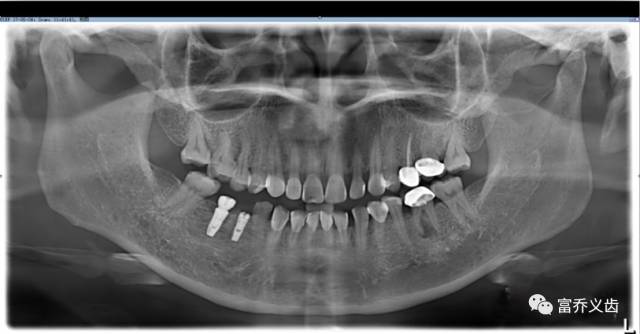

植入登腾种植体两颗

手术后CBCT以及曲面断层片